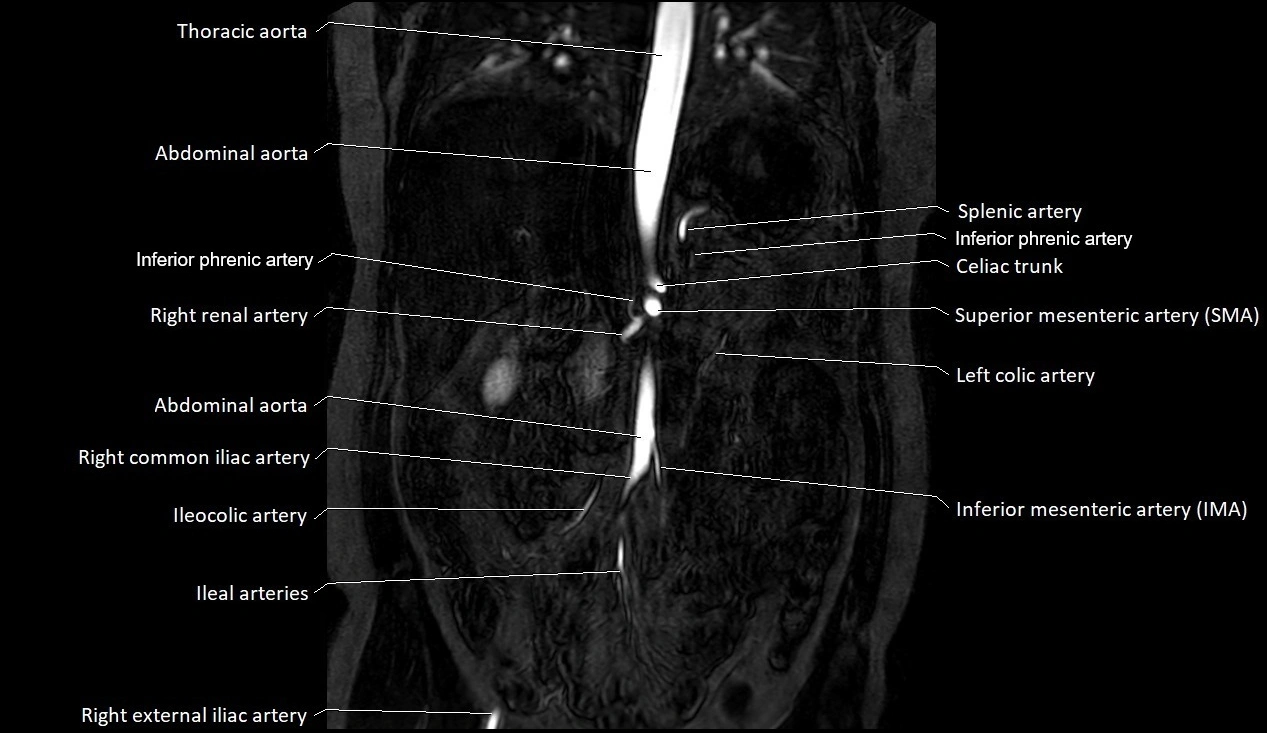

CT images

image